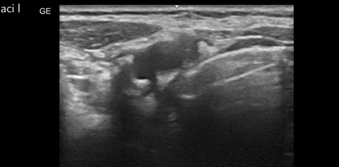

Bei einer Carotisstenose handelt es sich um eine Verengung der Halsschlagader (Carotis), die in den meisten Fällen durch Ablagerungen in den Blutgefäßen entsteht. Sie kann eine der Ursachen für einen Schlaganfall sein. Zu den Risikofaktoren gehören neben dem Rauchen auch ein erhöhter Blutdruck oder ein erhöhter Cholesterinspiegel. Die Therapie wird anhand des Ausmaßes der Verengung sowie dem allgemeinen Gesundheitszustand entschieden. Hierbei kann man sich zwischen einer konservativen Therapie und einer Operativen Therapie (z.B. Stentimplantation, TEA, Bypass, etc.) entscheiden.